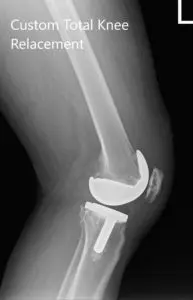

The implant used: Custom femoral implant with a custom tibial tray, with 8-mm polyethylene insert, with custom 35-mm x 7-m patellar implant.

Postoperative X-ray images of the left knee in AP and lateral view.